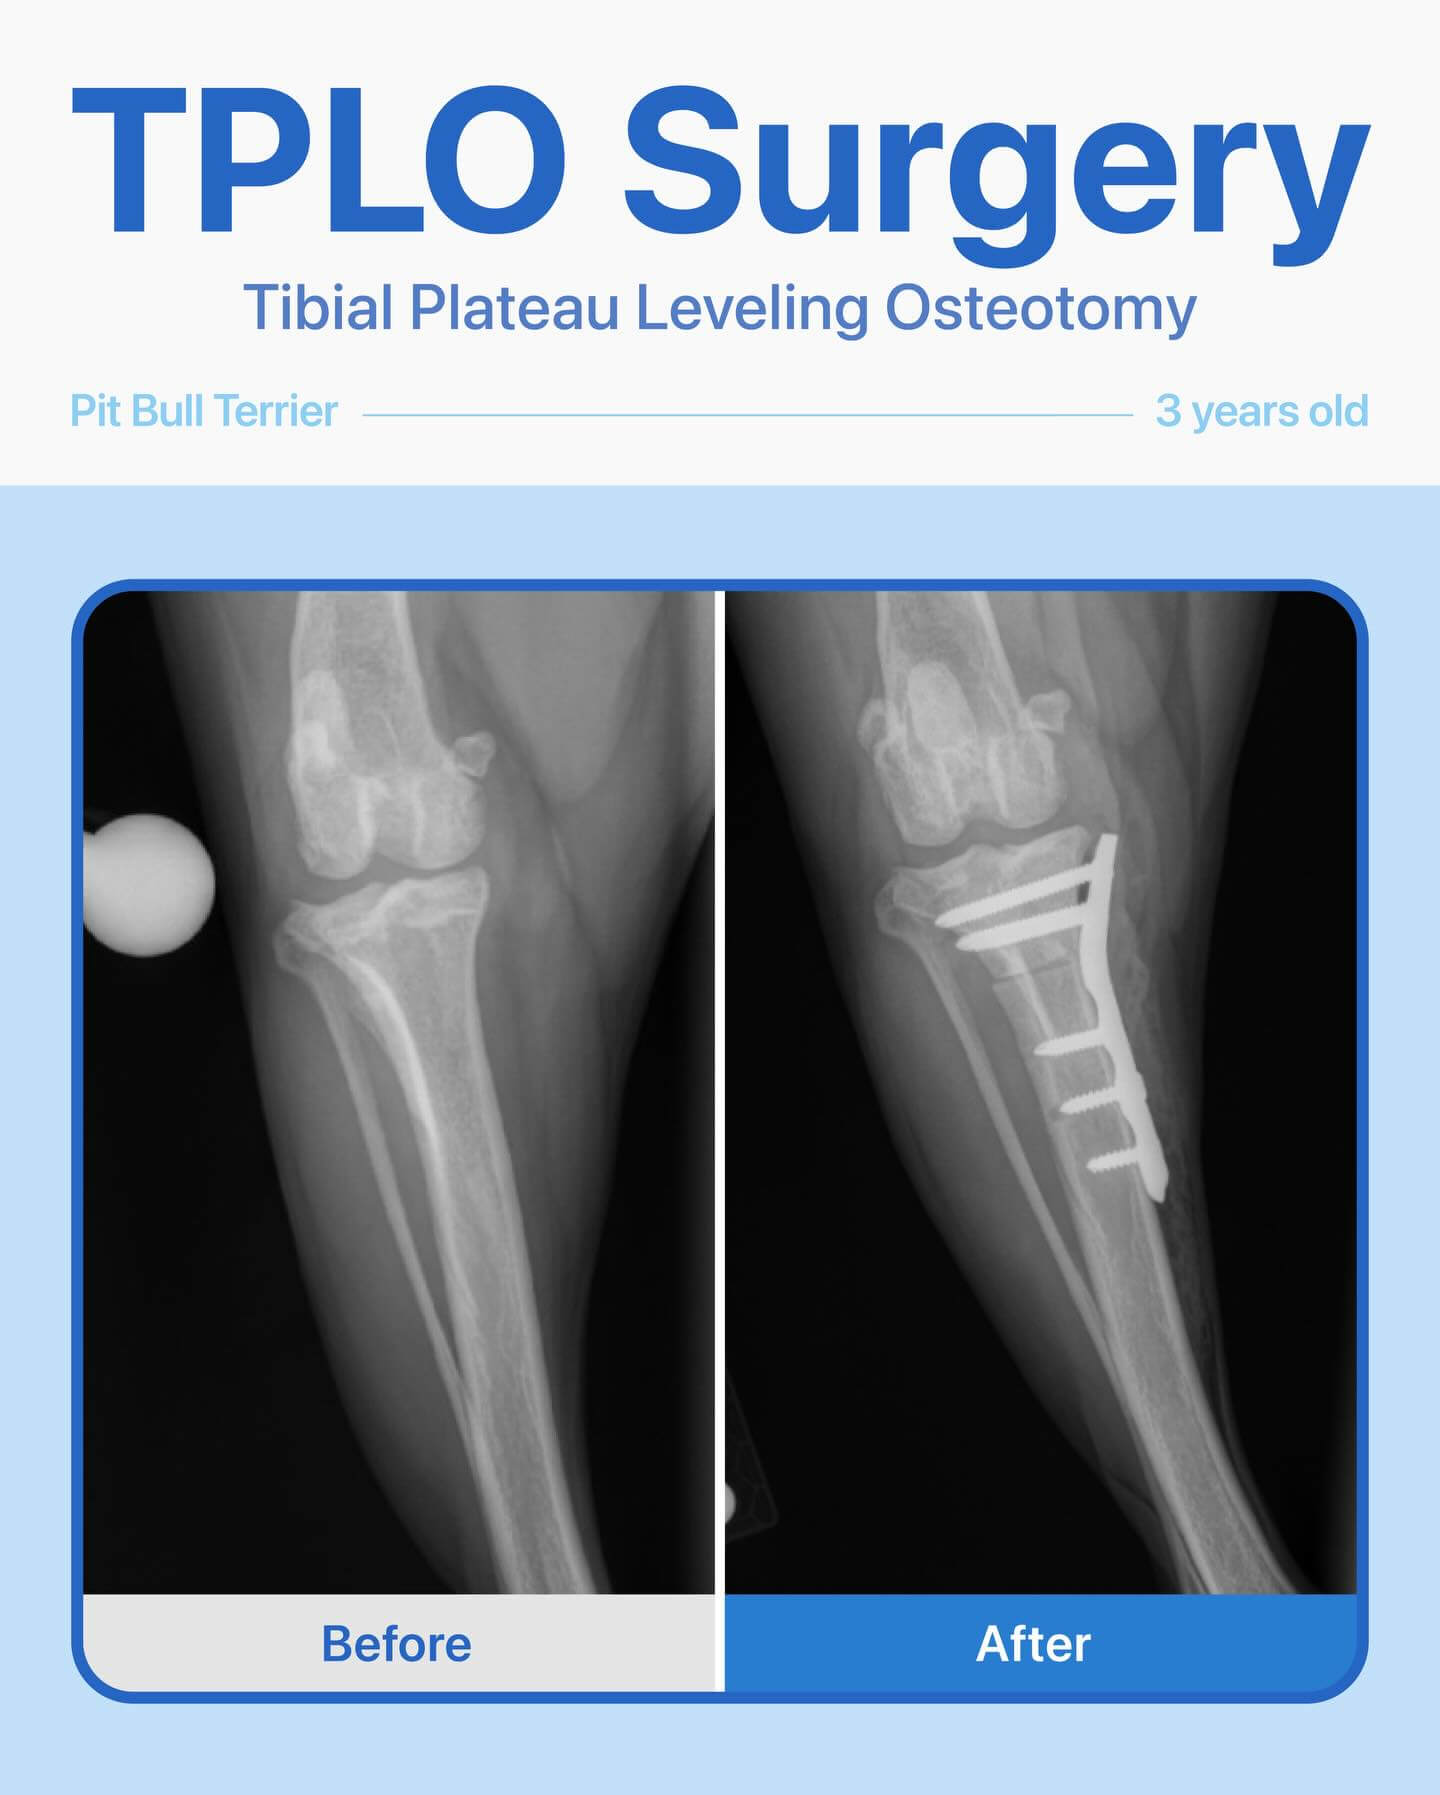

This 3-year-old female Pit Bull Terrier came to us unable to put weight on her left leg. Her owner wanted a second opinion, so we performed x-rays and a thorough orthopedic exam, which revealed a complete cranial cruciate ligament tear.

We recommended and performed TPLO surgery to stabilize her knee. Thanks to careful surgical technique and post-op care, she has made an amazing recovery — walking comfortably, running, and playing pain-free!